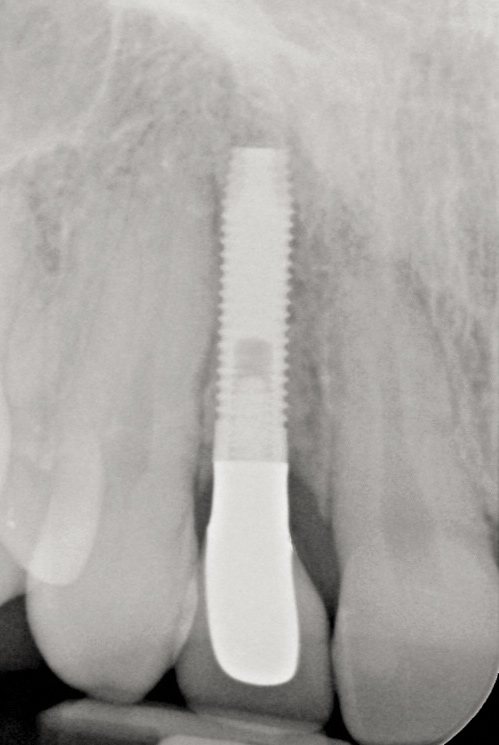

Fig 17. Radiograph showed symmetrical infrabony defect affecting 50% of the implant surface.

Figure 17

28. Seventeen-month post-treatment radiograph demonstrating bone close to the implant approximation and almost complete osseous fill of the original infrabony defect.

Figure 28